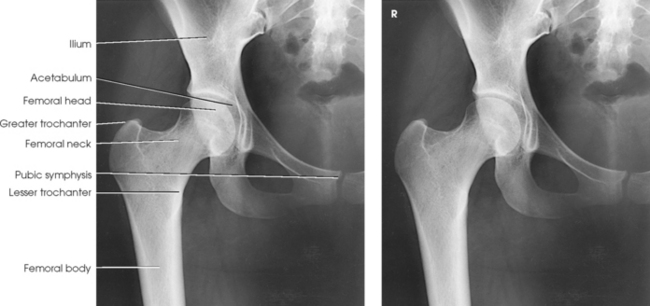

The hip bone consists of the ilium, pubis, and ischium (Figs. 7-1 and 7-2). These three bones join together to form the acetabulum, the cup-shaped socket that receives the head of the femur. The ilium, pubis, and ischium are separated by cartilage in children but become fused into one bone in adults.

The femur is the longest, strongest, and heaviest bone in the body. The proximal end of the femur consists of a head, a neck, and two large processes: the greater and lesser trochanters (Fig. 7-4). The smooth, rounded head is connected to the femoral body by a pyramid-shaped neck and is received into the acetabular cavity of the hip bone. A small depression at the center of the head, the fovea capitis, attaches to the ligamentum capitis femoris (Fig. 7-5; see Fig. 7-4). The neck is constricted near the head but expands to a broad base at the body of the bone. The neck projects medially, superiorly, and anteriorly from the body. The trochanters are situated at the junction of the body and the base of the neck. The greater trochanter is at the superolateral part of the femoral body, and the lesser trochanter is at the posteromedial part. The prominent ridge extending between the trochanters at the base of the neck on the posterior surface of the body is called the intertrochanteric crest. The less prominent ridge connecting the trochanters anteriorly is called the intertrochanteric line. The femoral neck and the intertrochanteric crest are two common sites of fractures in elderly adults. The superior portion of the greater trochanter projects above the neck and curves slightly posteriorly and medially.

Fig. 7-4 Proximal right femur. A, Anterior aspect. B, Medial aspect. The body is positioned 15 to 20 degrees posterior from head. C, Posterior aspect. D, Posterior aspect of right proximal human femur. Note anatomic details and compare with C.